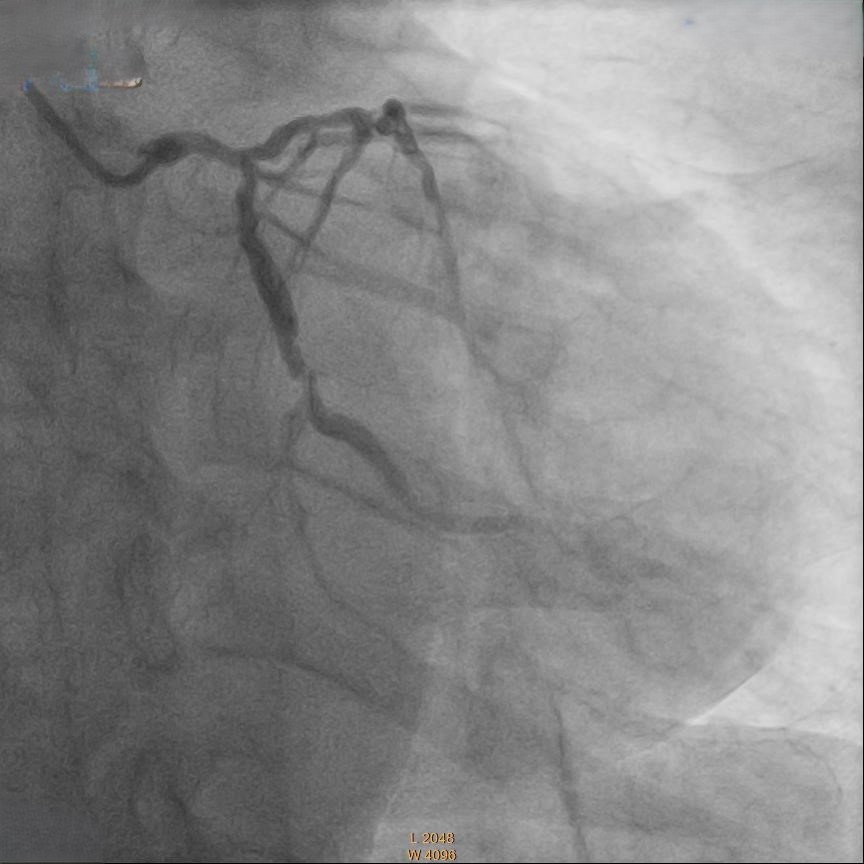

Relevant Catheterization Findings

Coronary angiography showed 50% stenosis at Left Main (LM), proximal to mid Left Anterior Descending Artery (LAD) 70% stenosis, 80% stenosis at mid Left Circumflex Artery (LCX) and Chronic Total Occlusion at mid Right Coronary Artery (RCA) with collateral from LAD.